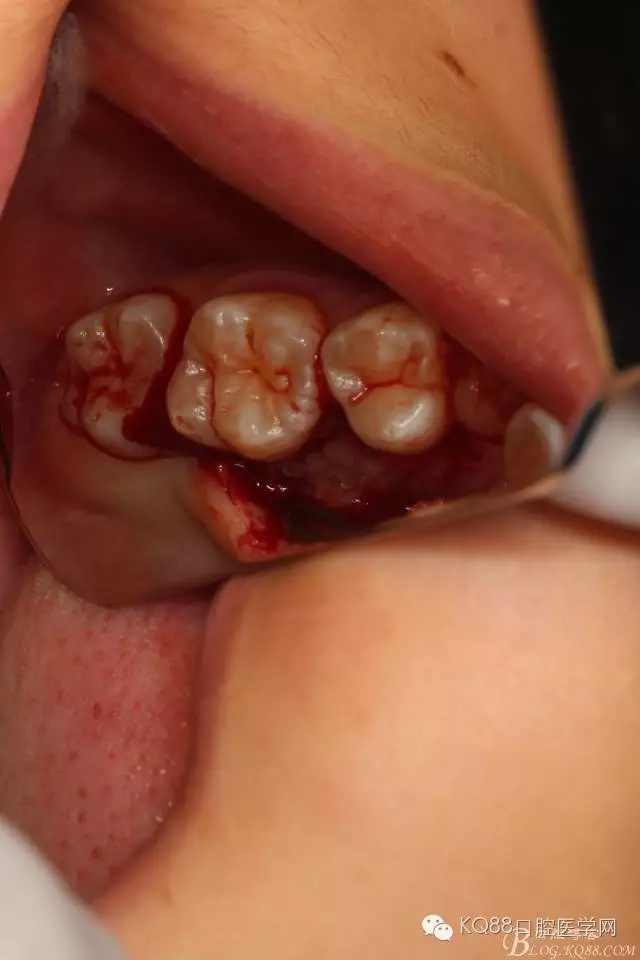

圖9.自23近中翻瓣中至26的遠(yuǎn)中,形成一個袋形口,暴露腭側(cè)骨面

圖11.小骨鑿去骨、露出25一小牙面

圖12.翻瓣后形成的袋形切口

圖13.骨鑿去骨后,用微創(chuàng)牙挺挺松25.

圖14.25的牙冠被挺松至齦緣處

圖15.順利拔除25,然后行頰側(cè)與腭側(cè)雙乳頭懸吊縫合,手術(shù)完畢